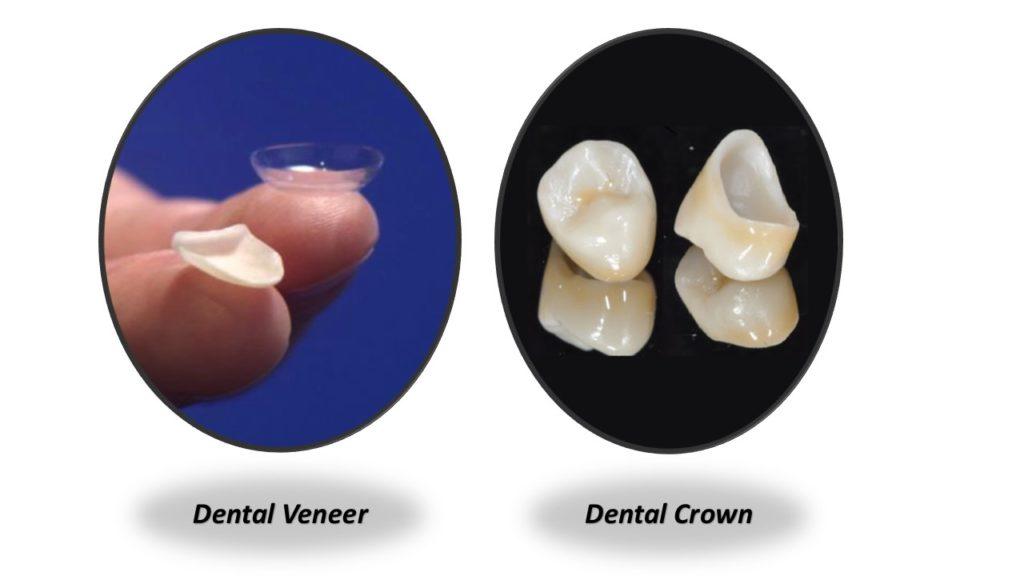

6️⃣ Q. WHAT’S THE DIFFERENCE BETWEEN VENEERS AND CROWNS?

A) A veneer is a thin shell that is applied to the front of your tooth. Crowns cover your teeth like a cap.